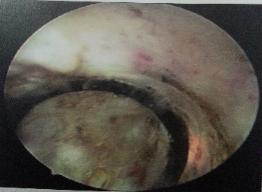

输尿管镜是经输尿管进行诊断、治疗的内镜设备,分为硬性输尿管镜和输尿管软镜。该器械可进行输尿管镜检查、输尿管镜下碎石取石术、输尿管镜取活检、电灼、肿瘤切除术等。

经尿道输尿管镜碎石术:为最常用的应用输尿管镜技术进行操作的手术。

1)经尿道置入导丝至患侧输尿管。

2)沿着导丝置入输尿管镜找到结石。

3)经输尿管镜工作通道置入钬激光光纤。

4)光纤对准结石击碎结石,并取出结石。

5)经输尿管镜置入双J管一根。

6)留置导尿。

术后当天即可正常下床活动、恢复正常饮食,术后2-3天即可出院,相比传统开放输尿管切开取石手术,极大的降低了手术创伤及手术并发症,没有刀口。